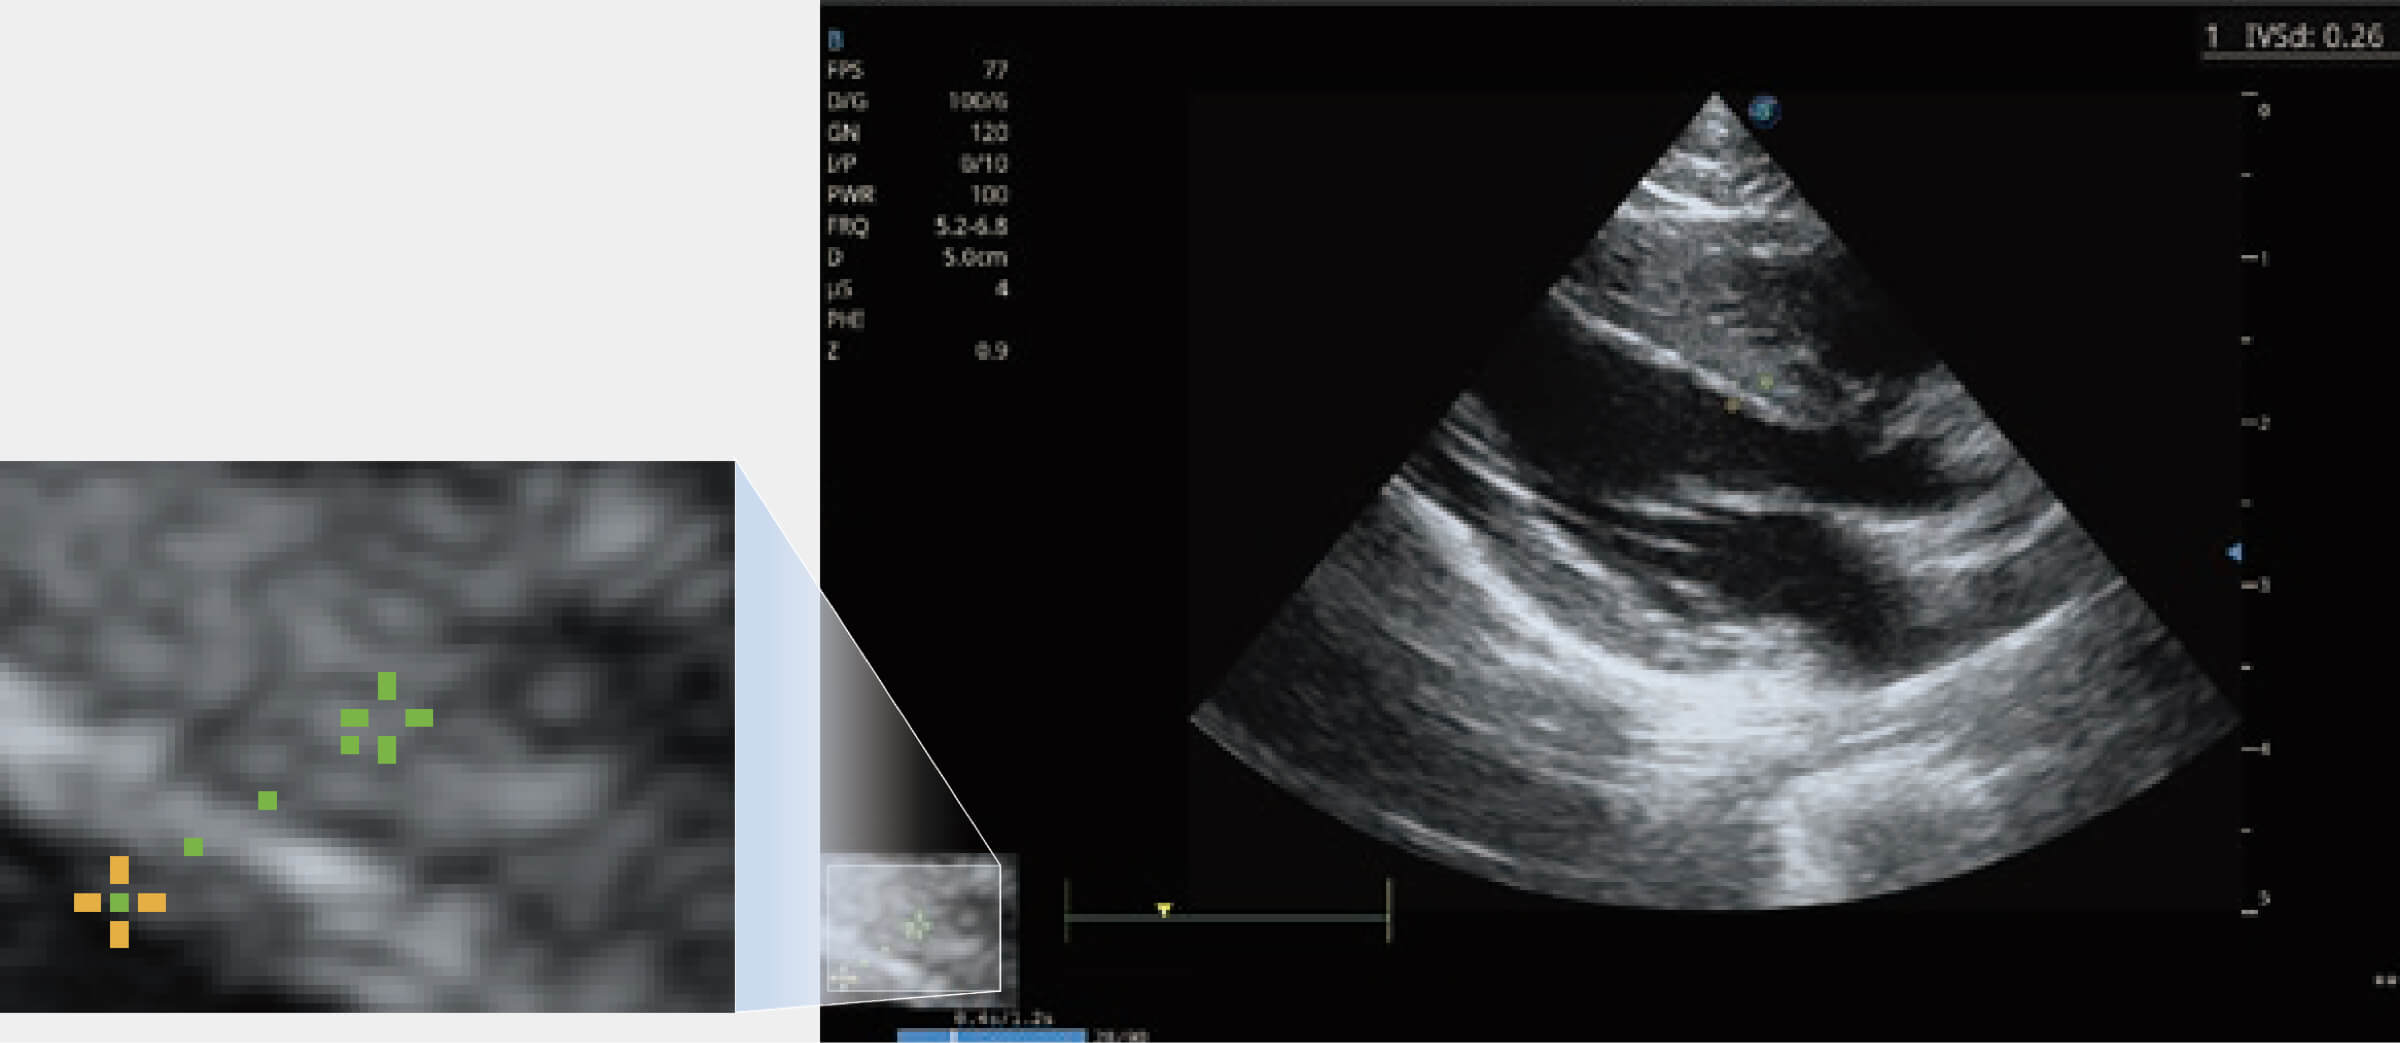

ProPet 70 進(jìn)一步提升了微米成像算法,更加注重對基礎(chǔ)原始圖像的還原和保留,在有效減少斑點(diǎn)噪聲、增強(qiáng)組織邊界顯示的同時,避免過度優(yōu)化丟失真實(shí)的解剖信息。

增強(qiáng)穿刺針在動物解剖結(jié)構(gòu)中的位置,提高穿刺介入的安全性和準(zhǔn)確性。

通過360度任意調(diào)節(jié)3條M型取樣線,在同一心動周期上觀察心臟不同位置的運(yùn)動曲線,得到準(zhǔn)確的心功能測量數(shù)據(jù),有效評估心肌運(yùn)動及左心室功能。

當(dāng)心臟測量結(jié)果超出正常范圍時,可實(shí)時預(yù)警提示動物醫(yī)生,減少疾病漏診概率。